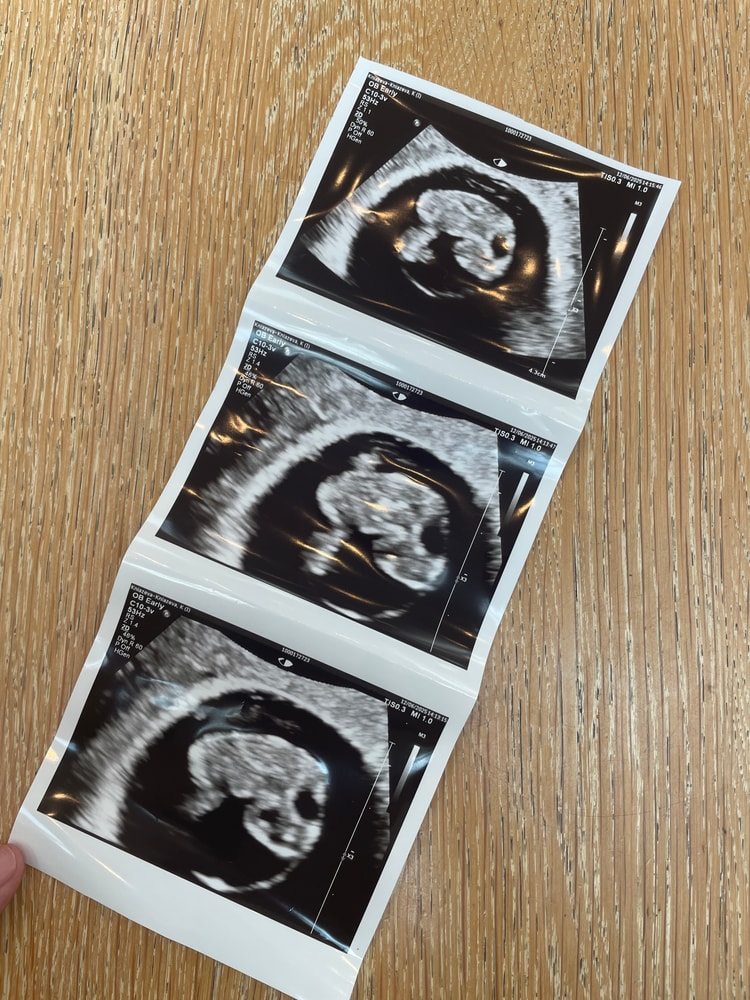

38 дпп УЗИ

Результаты УЗИ

Обалдеть , какой большой малыш😍 мы виделись , когда ты был 2 мм, а теперь уже целых 15 мм 😍 врач сказал, все синонимы слова «красивый» на английском. А я смотрела, как бьется сердечко, и расплывалась в улыбке🥹♥️ расти малыш, увидимся на первом скрининге 😍